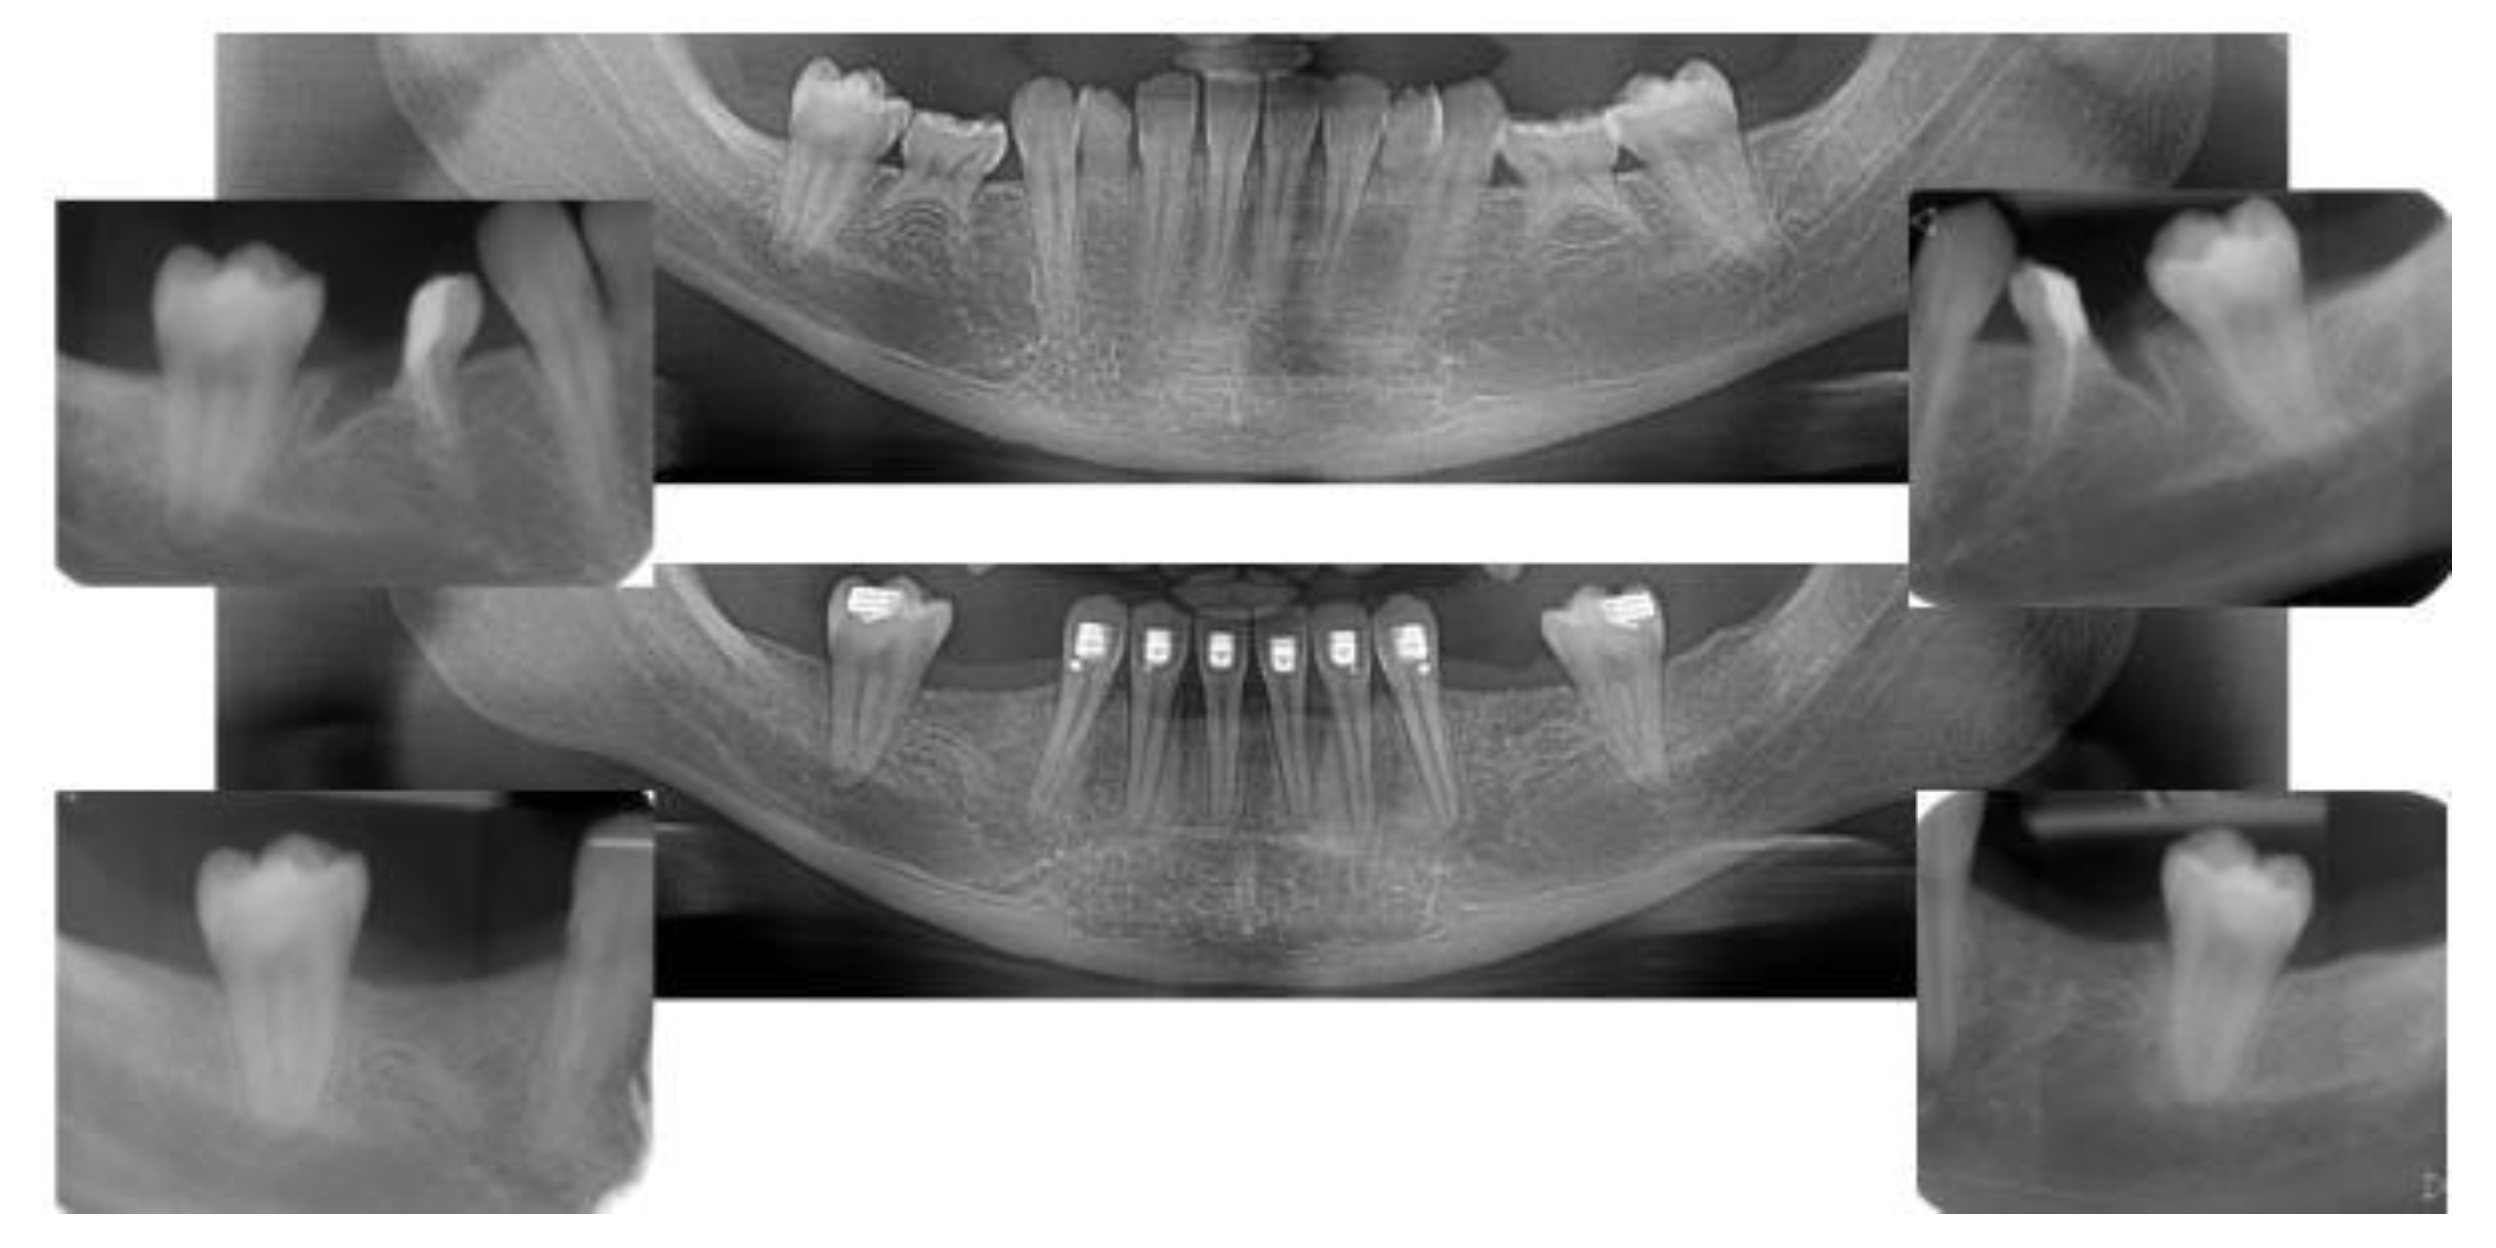

2.5. Individual Cases Description

- Case 1:

- Case 2:

- Case 3:

- Case 4:

- Case 5: